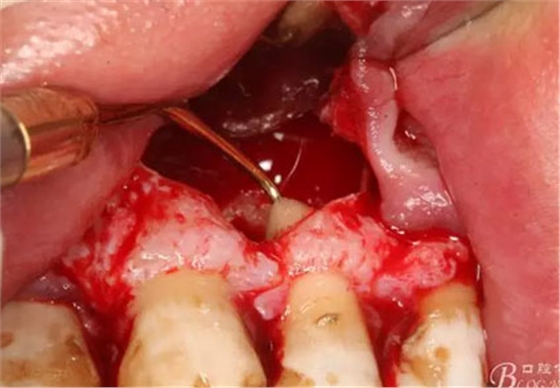

圖15.摘除的囊壁

圖16.囊壁摘除后22牙根懸浮在骨腔內(nèi)